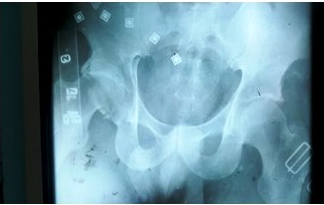

Dicho paciente fue atendido en el momento de su recepción en el área de código rojo, se valoró y se siguió el protocolo vigente para la atención de los pacientes politraumatizados implementado en nuestro centro. Se realizaron radiografías de las zonas afectadas, incluida una tomografía de la pelvis ósea. (Figuras 1 y 2).

Tras su control en dicha área se diagnosticó una fractura intraarticular del tercio distal del radio derecho y una fractura luxación posterior de cadera derecha.